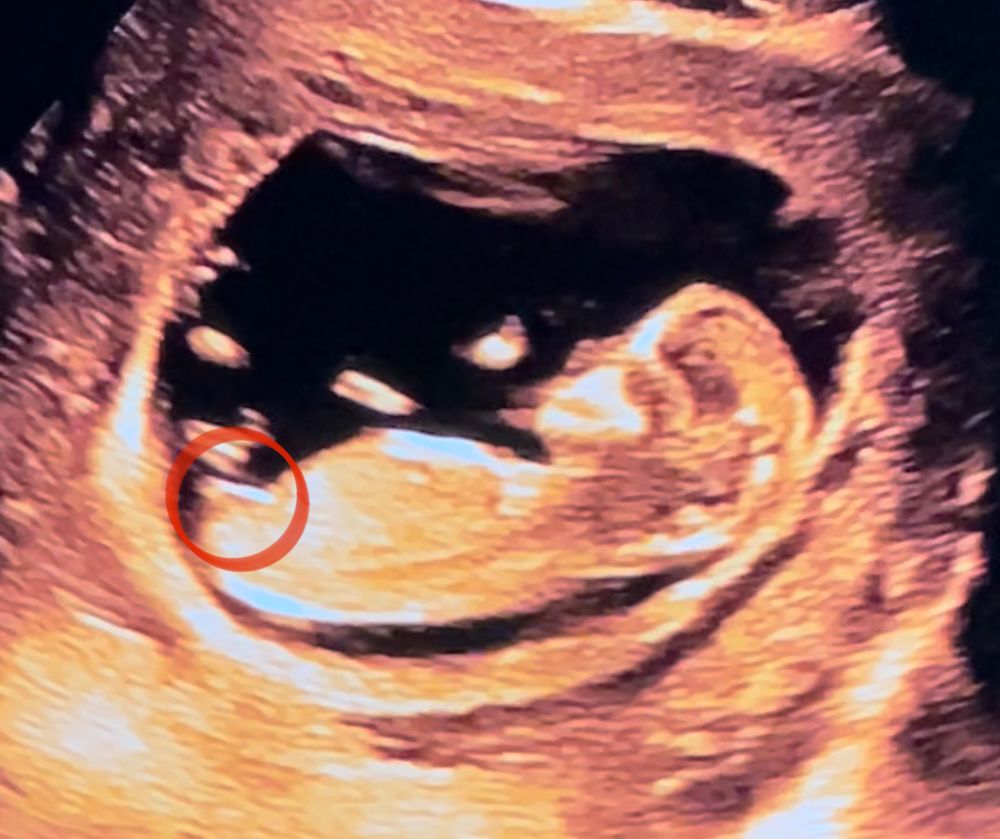

100% девочка. Это же не гадание на кофейной гуще, а достоверный метод исследования) Полосочка-это половой бугорок, если «встанет» наверх углом более 30 градусов от параллели тела Изображение , то потом преобразуется в половой член, а если вниз «ляжет», то клитор. Синяя-параллель тела, а зелёненьким ваш угол к ней, получается менее 30 градусов, значит дамочка. А если бы было более 30- как фиолетовым, тогда бы был парень)

Аня, а тут кого видно? Я почему-то сомневаюсь, что в кадре есть половой бугорок... Но, может, это он? Изображение Автор, извините, что влезла.

да, если половой бугорок параллельно позвоночнику, как у вас, то девочка.

Да, тоже больше видится девочка. Белая полосочка - это половой бугорок.